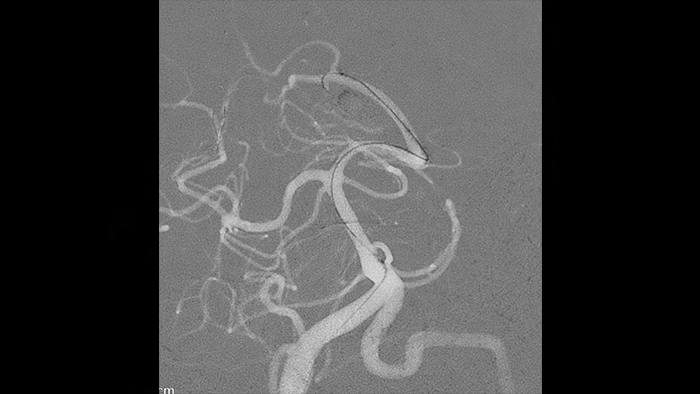

Lorsque vous surveillez des MAV au fil du temps, des artefacts de soustraction peuvent masquer des informations cliniques. La fonction de recalage automatique des pixels unique de Philips, ClarityIQ, permet de supprimer les informations susceptibles d’être trompeuses, en temps réel et sans intervention de l’utilisateur.

Pendant le traitement, les artefacts de soustraction peuvent masquer la direction dans laquelle les agents emboliques liquides se déplacent. L’utilisation de la fonction de recalage automatique des pixels dans notre solution ClarityIQ vous permet de visualiser la direction dans laquelle l’agent embolique liquide se déplace et son arrivée.

Le mode de collage Roadmap Pro filtre les vaisseaux déjà embolisés, ce qui vous permet de vous concentrer sur le produit que vous injectez et sur sa diffusion.